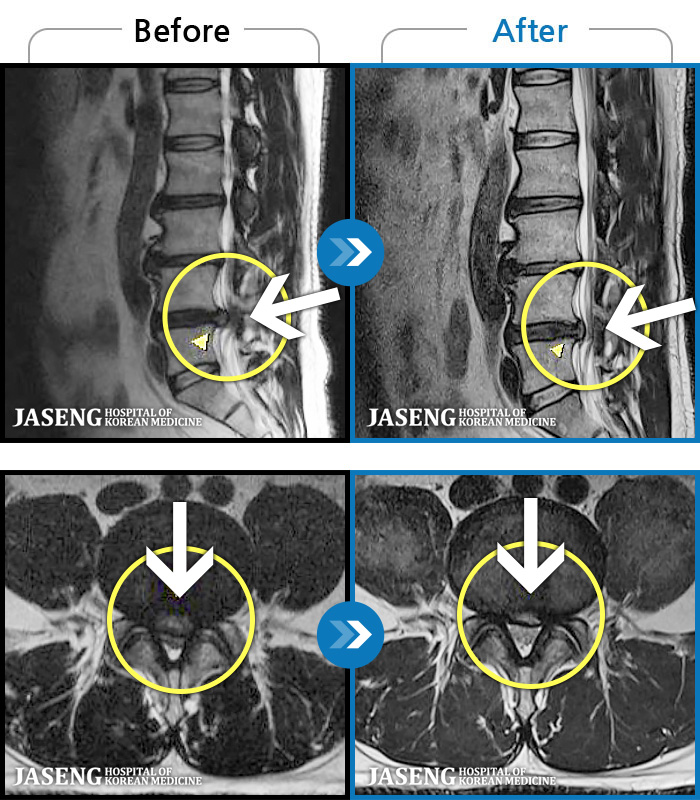

- MRI ġ

MRI ġ

94 MRI ũ ʸ Ȯϼ.